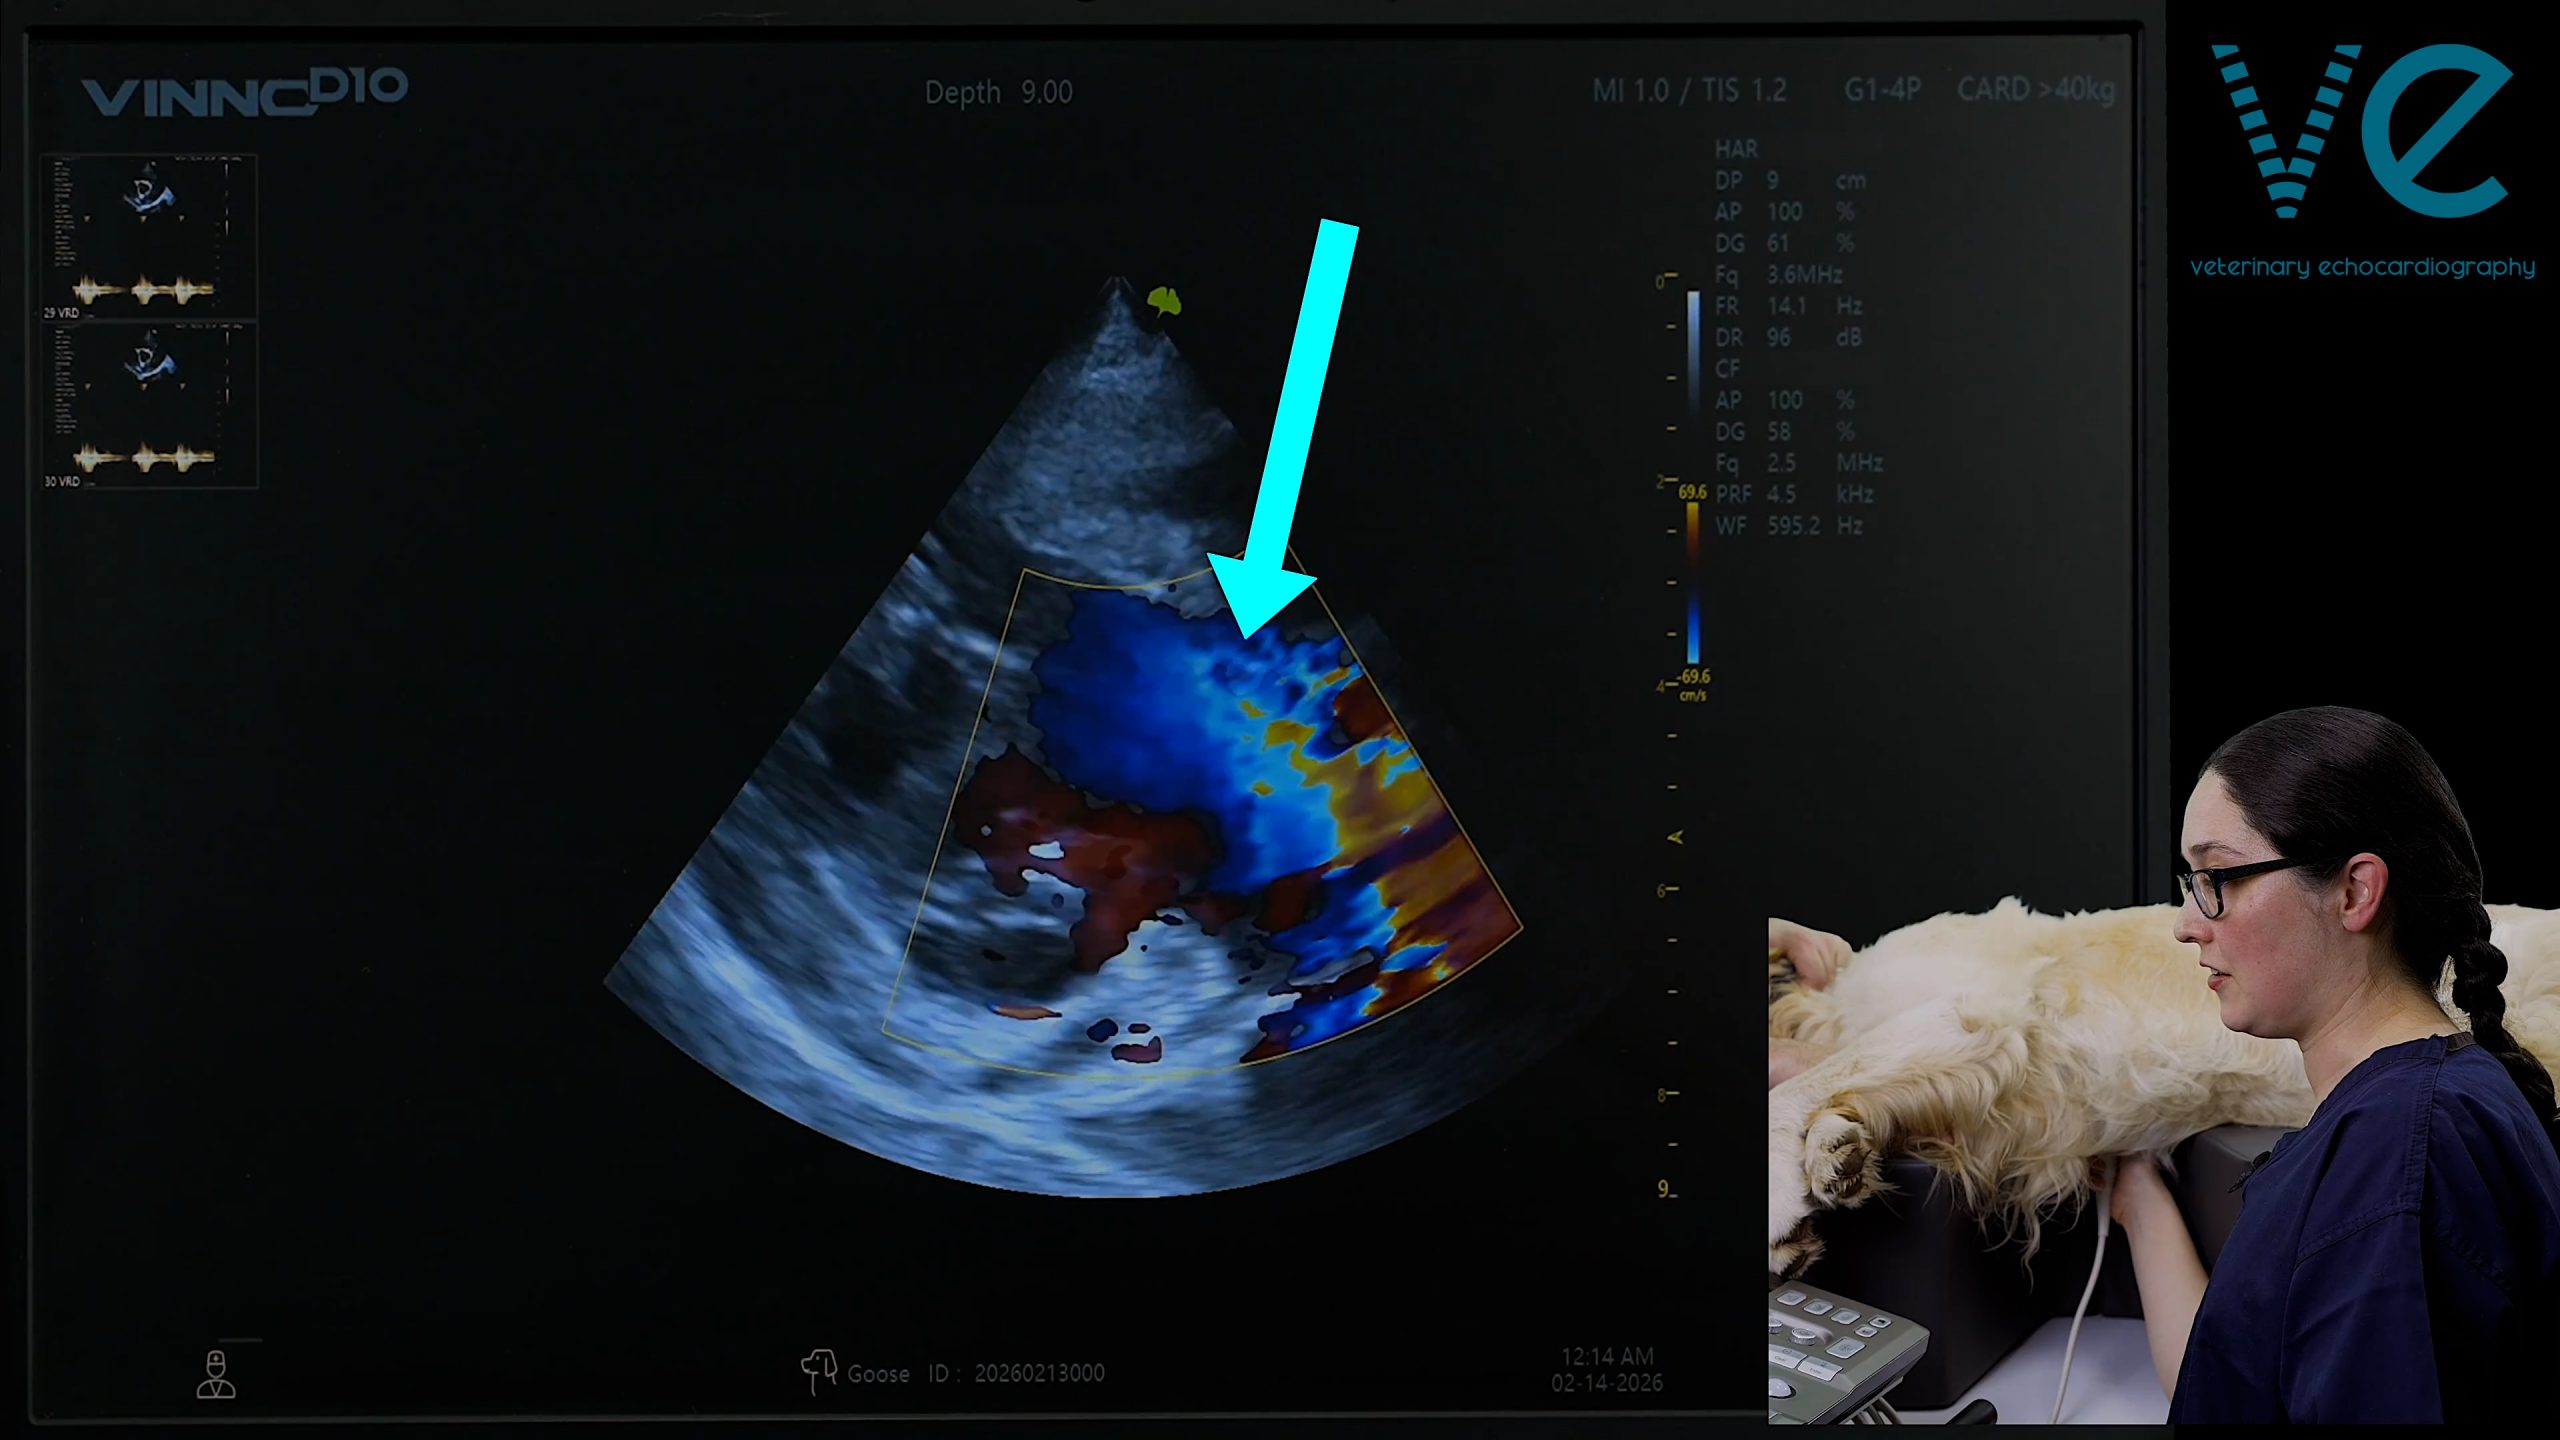

3 useful colour views for interrogating perimembranous VSDs

A kitten or puppy with a loud murmur always raises suspicion of a restrictive ventricular septal defect (VSD). ‘Restrictive’ sounds bad, but it’s actually the best case scenario for a